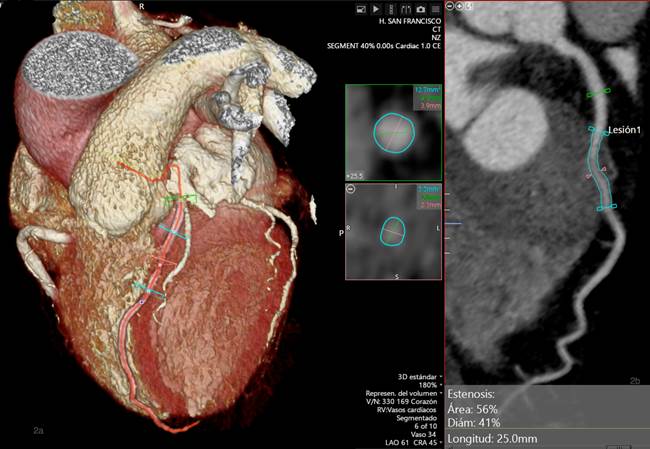

Para la estimación de la estenosis, se comparó el área más estrecha del segmento puenteado con el área del segmento previo al PM en vista MPR curvado, obteniendo una estenosis del 56% en sístole (fase 40%) y 39% en diástole (fase 0%) (Figs. 2 y 3).